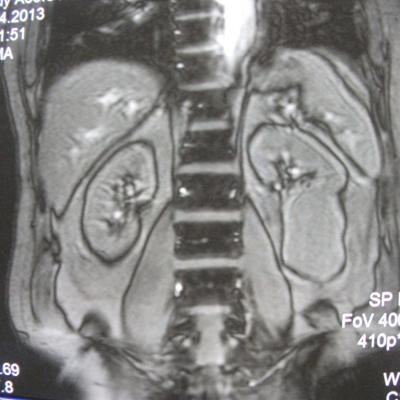

такое заключение: Левая почка: расположена обычно, увеличена, общими размерами около 13х5,5см. В области средней и нижней трети почки определяется объёмное образование неправильной формы, деформирующее наружный контур почки, распространяющиеся с чашечно-лоханочную систему. Опухоль имеет четкие неровные бугристые контуры с наличием псевдокапсулы, неоднородной структуры с признаками распада, максимальными размерами около 78,7х47х48мм